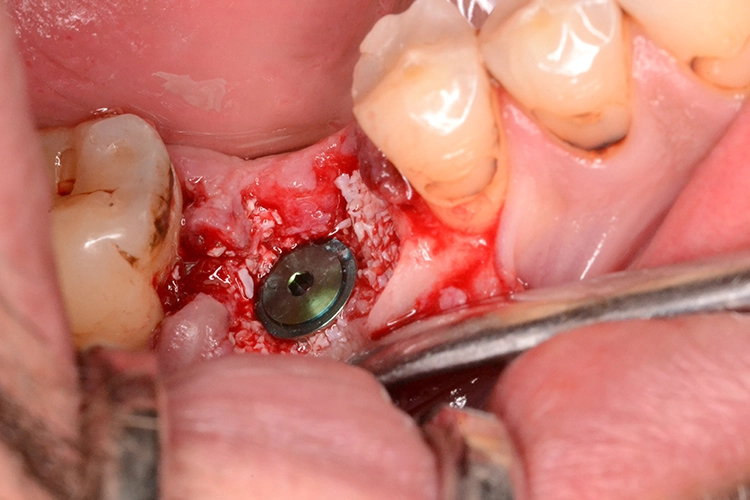

Im Anschluss an die Implantat-Insertion stellt sich die Frage nach den Spalträumen zwischen Implantat und Alveole im crestalen Bereich, die sogenannten Jumping Gaps. Bezüglich des Verfahrens mit diesen Spalträumen gibt es unterschiedliche Ansätze. So sieht man bei kleineren Spalträumen von weniger als 1 mm in der Regel davon ab, diese zu verfüllen.

Bei größeren empfiehlt sich unter Umständen ein Auffüllen der Lücken. Vor allem, wenn man im Molarenbereich das Implantat im Septum inseriert hat, sollte man die Alveolen auffüllen. Jedoch ist zu bedenken, dass ein Verfüllen mit Knochenmaterial möglicherweise die vollständige Deckung des Wundgebietes nach sich zieht, was unter Umständen mit der minimalen Schnittführung bzw. flapless Variante nicht zu vereinen ist.

Eine vom Autor favorisierte Möglichkeit stellt daher das Verfüllen dieser Spalträume statt mit einem Knochenersatzmaterial mit a-PRF nach Choukrun dar. Natürlich ist auch ein Gemisch von Knochenersatzmaterial und a-PRF (sog. Sticky Bone) eine Option, wobei die Alveole dann auch mit einem Kollagenpunch oder einer Gewebestanze aus dem Gaumen gedeckt werden kann. Ein solch aufwendiges Verfahren zur Deckung sollte vor allem in Fällen von Frontzahnimplantaten mit dünnem Gingivatyp, hoher Lachlinie und hohen ästhetischen Ansprüchen des Patienten zur Anwendung kommen.